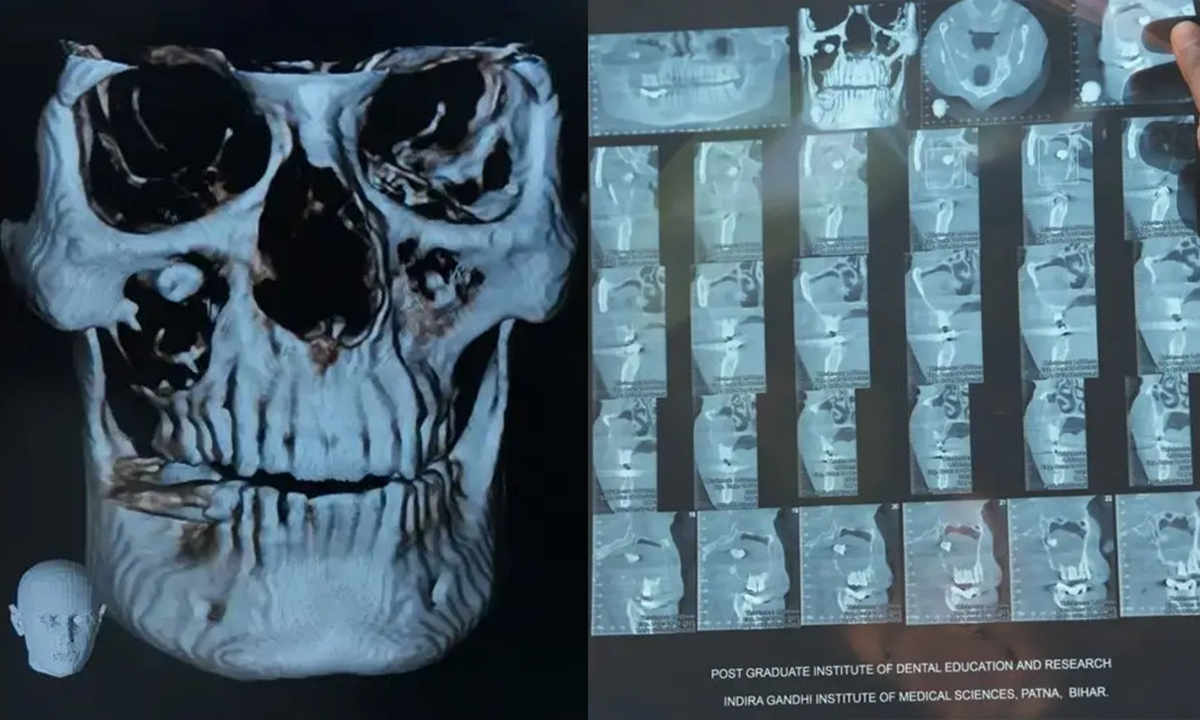

রমেশ কুমার বলেন, ‘ওই পিণ্ডের কারণে আমার দৃষ্টি ঝাপসা হয়ে গিয়েছিল। মাথার ডান দিকে যন্ত্রণা হচ্ছিল। এর ফলে আমার মাথা ঘুরত, ক্লান্তও লাগত। মনে হতো সব সময় শুয়ে থাকি। আমার সব কাজ আটকে গিয়েছিল। এরপর জুন মাসে আমি আইজিআইএমএসে দাঁতের চিকিৎসকের কাছে যাই। চিকিৎসক আমার সিবিসিটি স্ক্যান করান। সেখান থেকে জানতে পারি আমার চোখে দাঁত গজিয়েছে

সিবিসিটি সিস্টেম এমন এক ধরনের ডায়াগনস্টিক ইমাজিং ট্যুল যেখানে এক্স রে রশ্মি ব্যবহার করে হাড় ও সফ্ট টিস্যু, বিশেষত মাথা ও মুখ বা ‘ওরাল’ এরিয়ার হাই রেজোলিউশনের থ্রি-ডি ইমেজ পেতে সাহায্য করে।

রোগী রমেশ কুমারের যখন ‘কোন বিম কম্পিউটেড টোমোগ্রাফি’ বা সিবিসিটি করানো হয়, তখন দেখা যায়, তার দাঁতের গোড়া ‘ফ্লোর অব দ্য অরবিটে’ রয়েছে।

ডা. প্রিয়ঙ্কর সিং ব্যাখ্যা করেছেন, ‘এই ক্ষেত্রে, দাঁতের গোড়া ছিল ফ্লোর অফ অরবিটে। যদিও এর ক্রাউন (দাঁতের সাদা অংশ) ছিল ম্যাক্সিলারি সাইনাসে। যেহেতু এই দাঁত নিজের স্বাভাবিক স্থানে গঠিত হয়নি, তাই শরীরের কাছে এটা ফরেন বডি ছিল। শরীরের প্রতিরক্ষা ব্যবস্থা এই ফরেন বডি থেকে বাঁচার জন্য চারপাশে একটা সিস্ট ( সহজভাবে বলতে গেলে এক জাতীয় থলি) তৈরি করেছিল। এই সিস্টটাই তার পুরো ম্যাক্সিলারি সাইনাস এরিয়াকে ঘিরে রেখেছিল। এই কারণে তার মুখের ওপর ফোলাভাব ছিল এবং উপরের চোয়ালের হাড় গলছিল।’